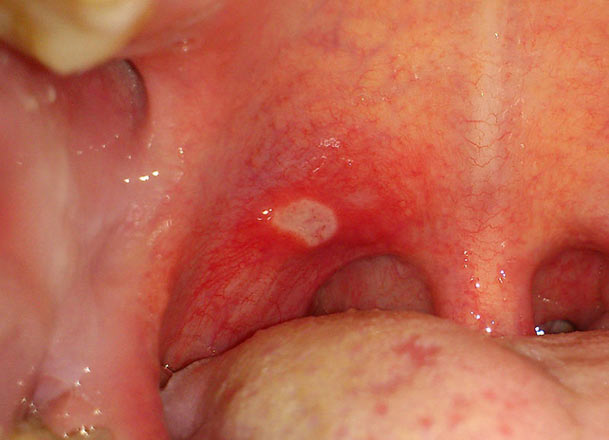

Red bumps on the roof of my mouth? – throat ent gland …

White Spots on Throat: Top 10 Causes with Treatments